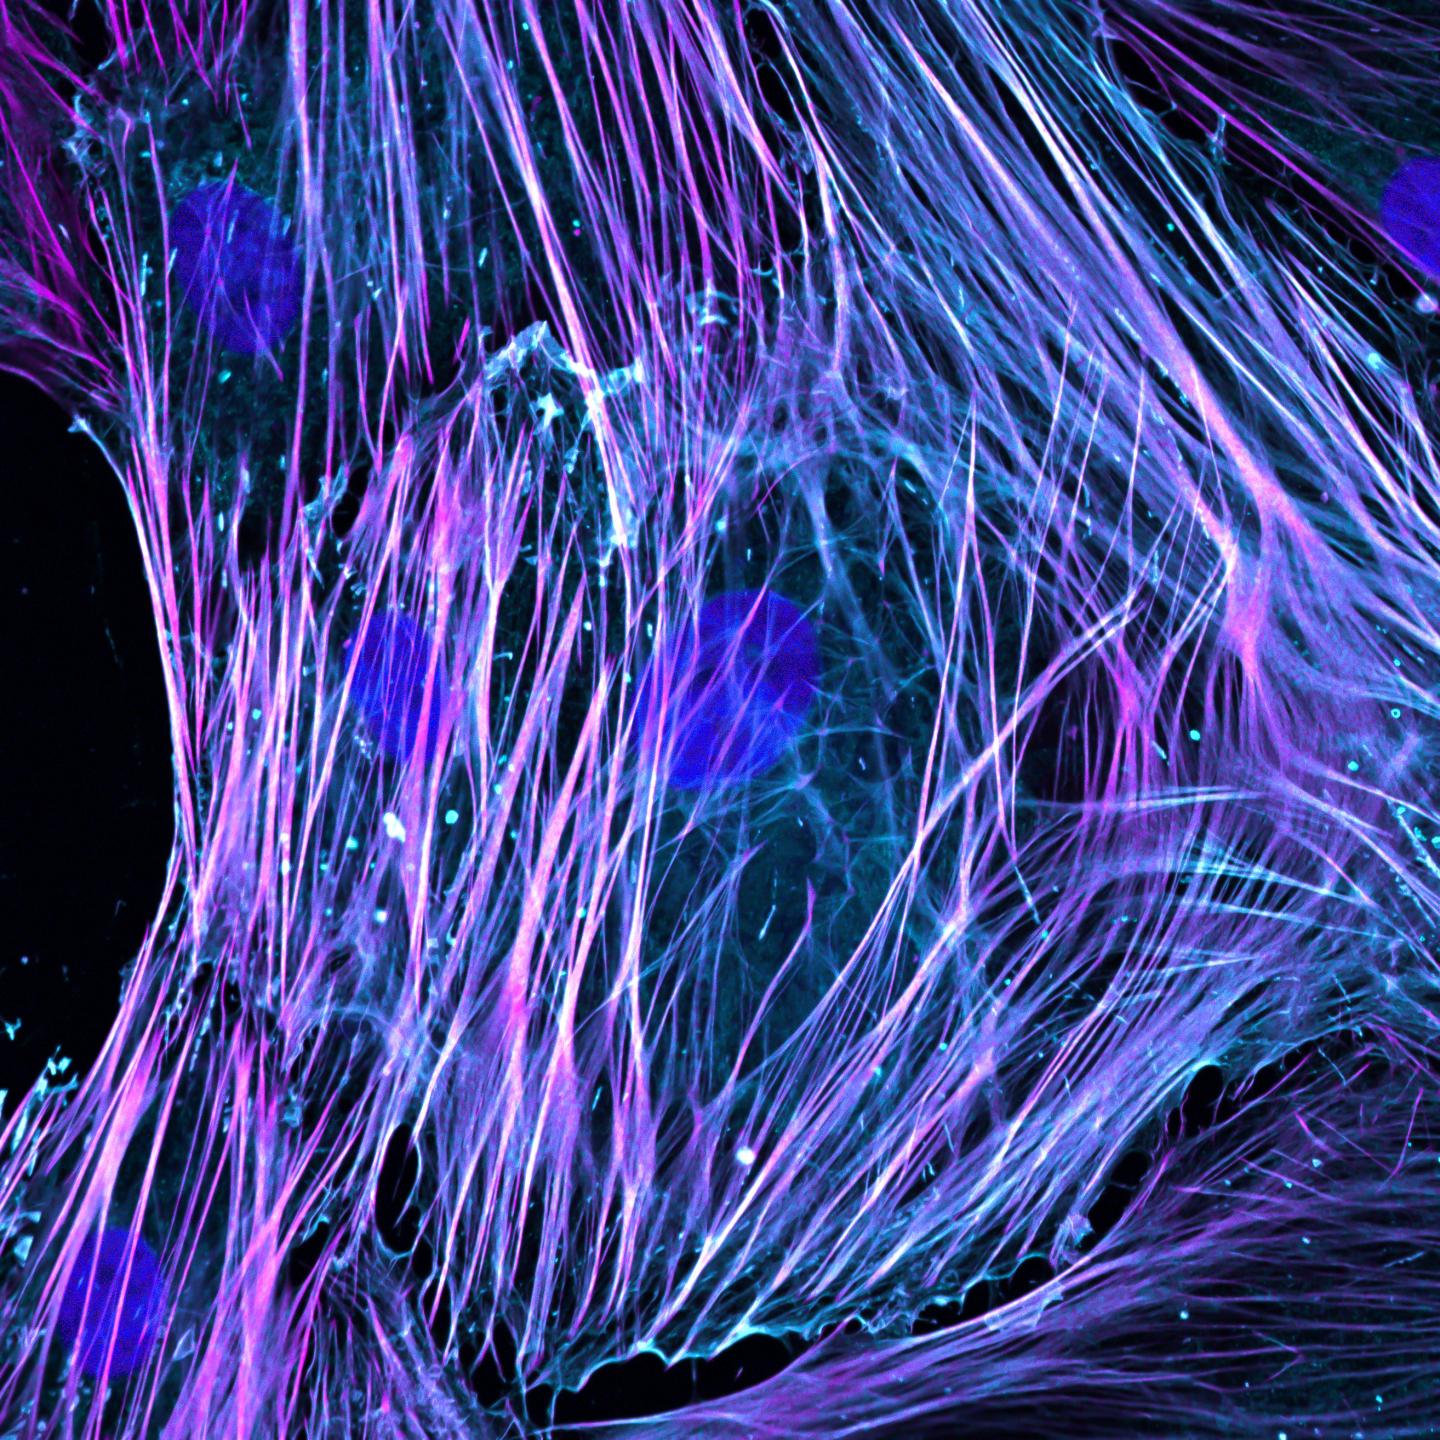

Activated Fibroblasts

image: High-resolution fluorescence imaging of activated fibroblasts with immunostaining of nuclei (DAPI, blue), ACTA2 (purple) and F-actin (phalloidin, cyan) showing stress fibre formation. view more

Credit: Wang Mao, Duke-NUS Medical School